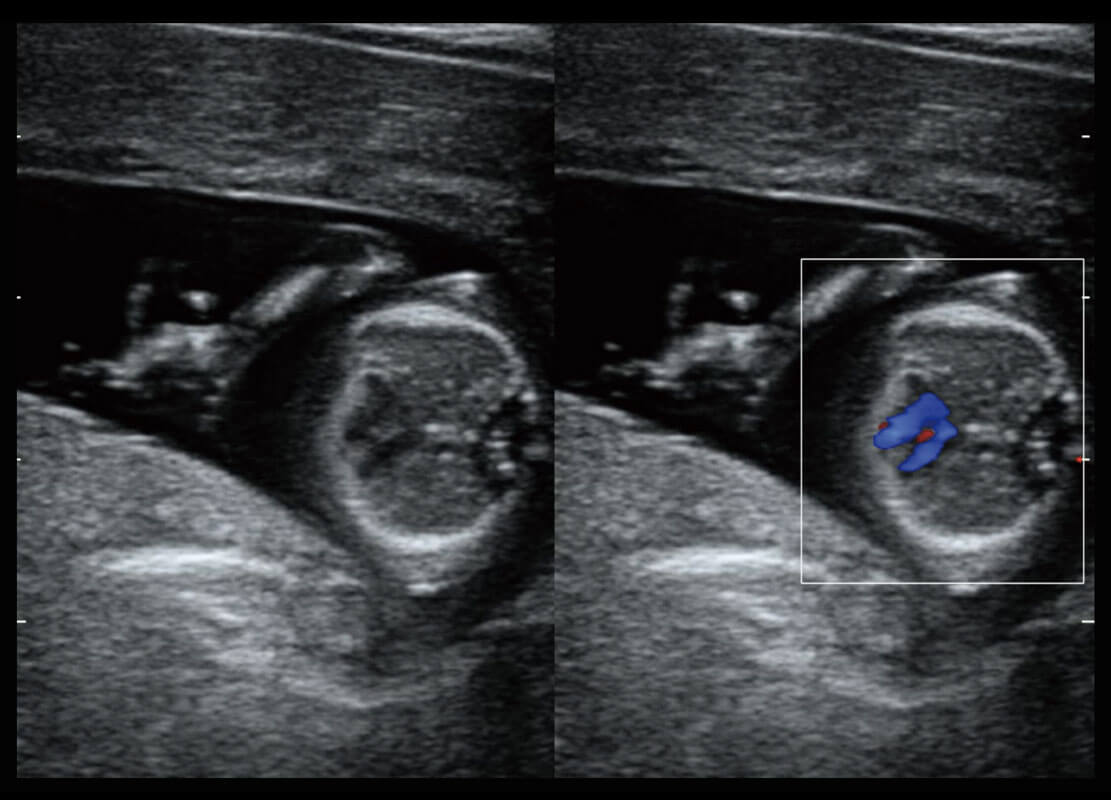

早孕-胎心

P60搭载一系列胎儿心脏成像技术,实现精细的胎儿心脏评估。

四腔切面

四腔心血流